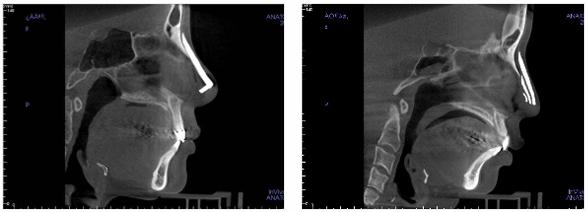

3、利用3DCT扫描,进行隆鼻失败修复

确认之前隆鼻手术的不自然、炎症、斑痕等状态,还确认之前手术使用的假体种类、大小、厚度、弯曲程度,还可以确认假体是否使用在全鼻。确认是否使用过鼻中隔软骨,并判断鼻中隔软骨、耳软骨、胸软骨中选择哪一种。手术不仅要满足顾客的美观,避免再手术的副作用,使手术达到***无误。